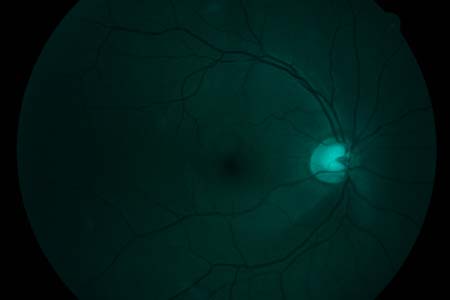

Oftalmo-neurologická diagnostika 1956, Michelem popsaný obraz si můžeme kdykoliv vyvolat, vyšetřujeme-li oční pozadí podle Vogtova návrhu bezčerveným světlem.